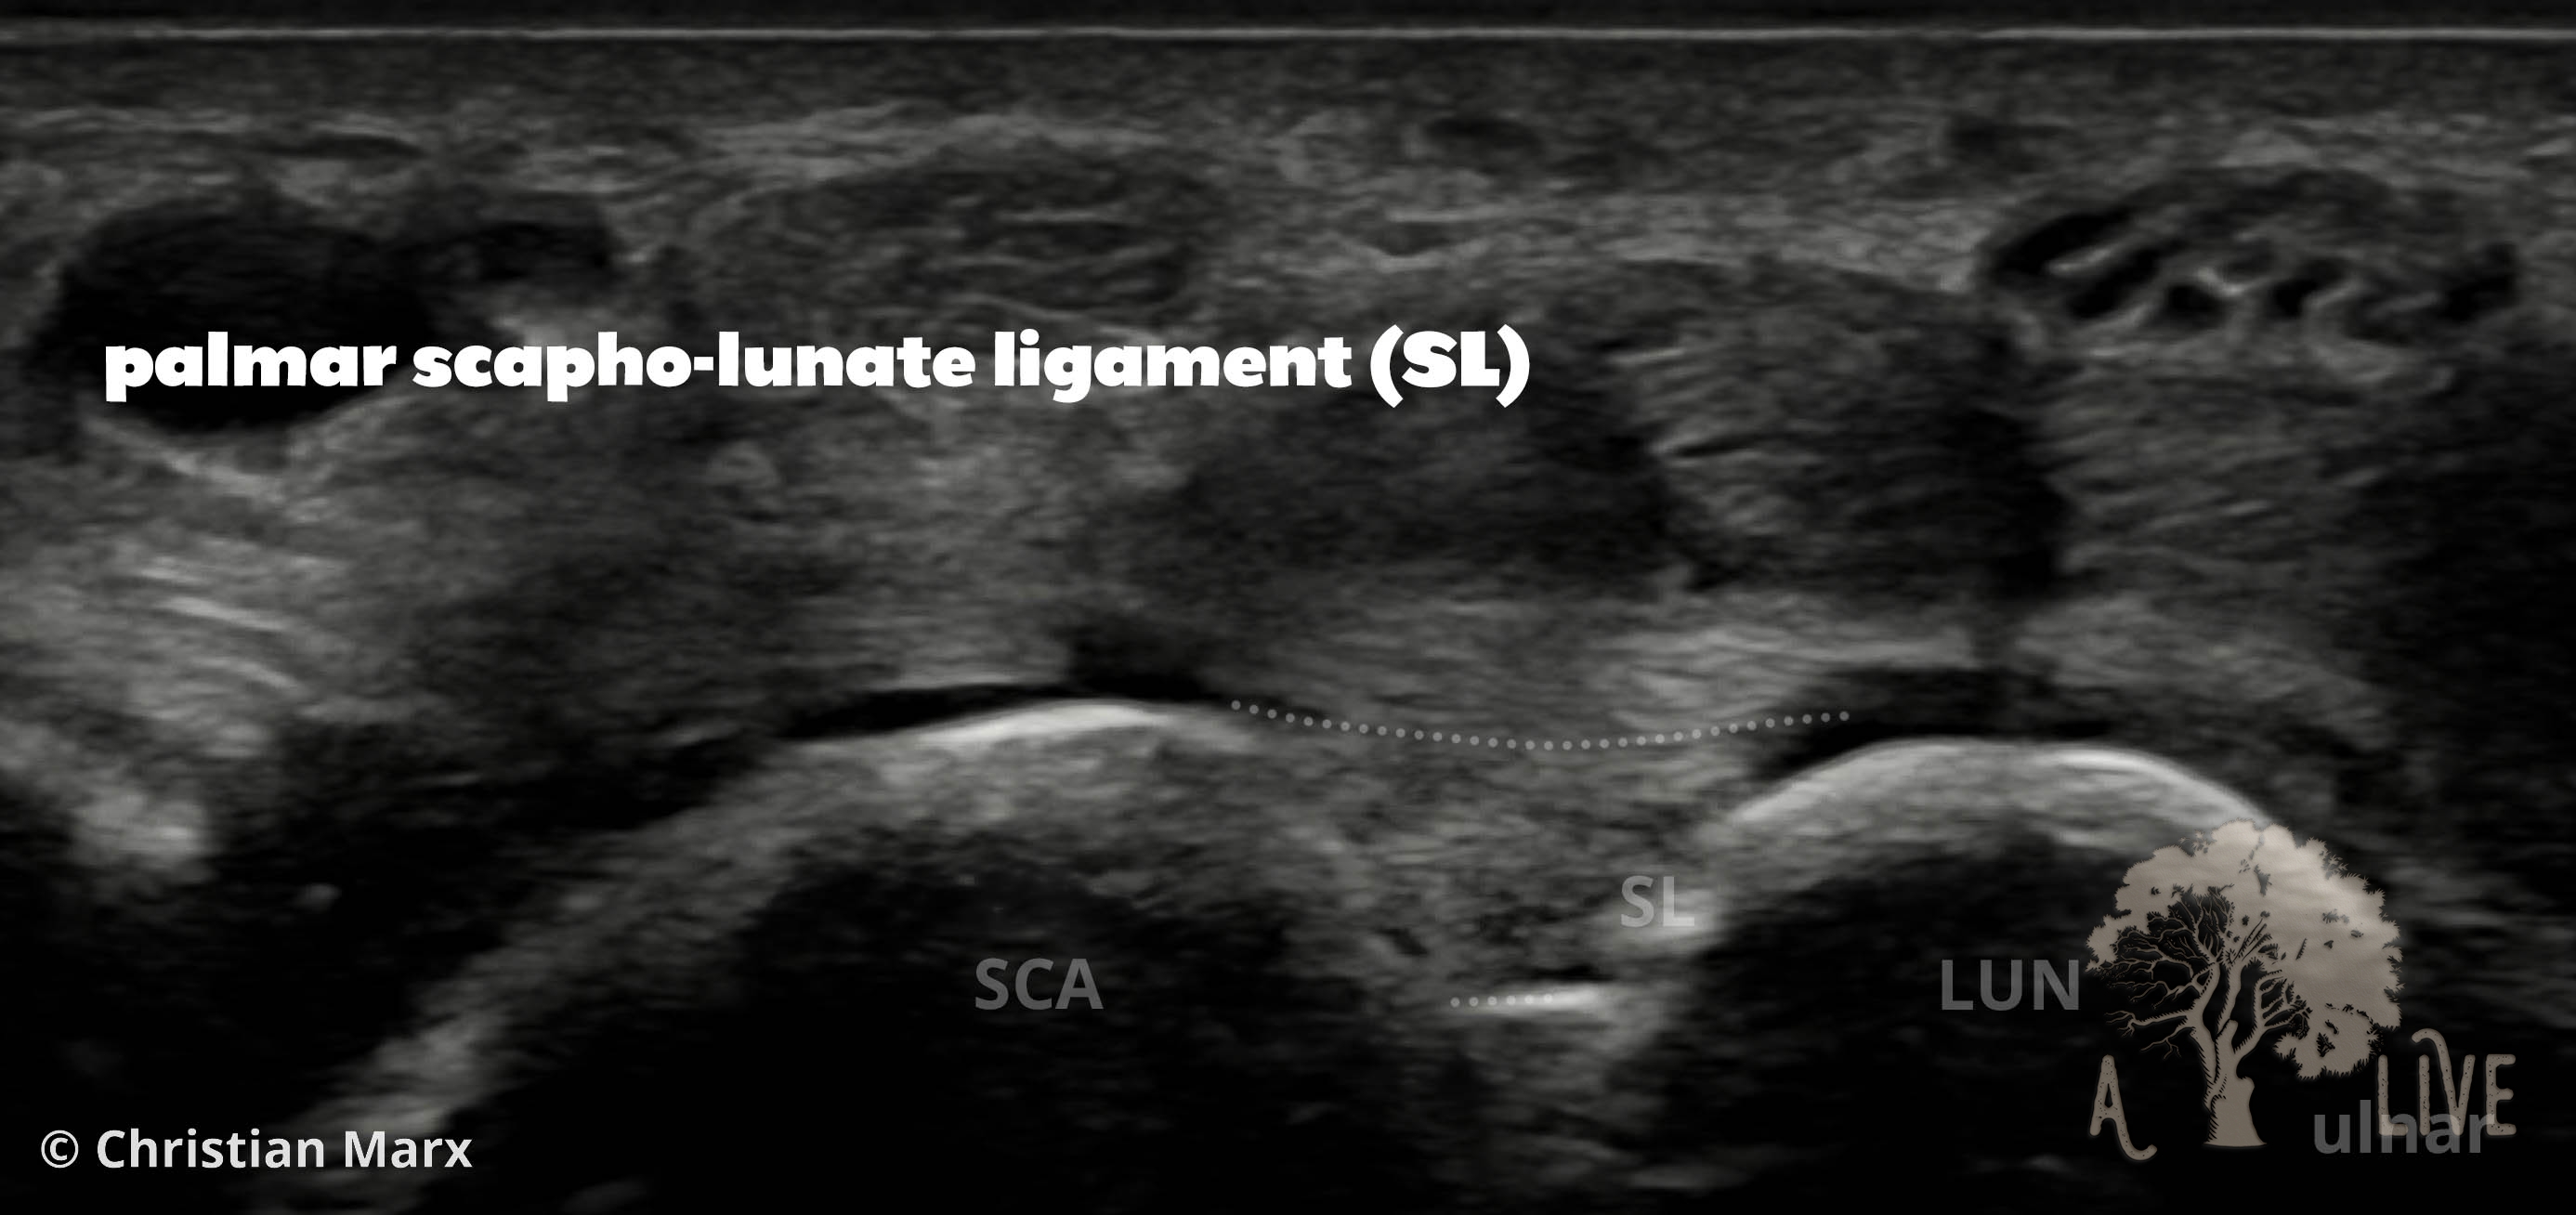

carpal ligaments